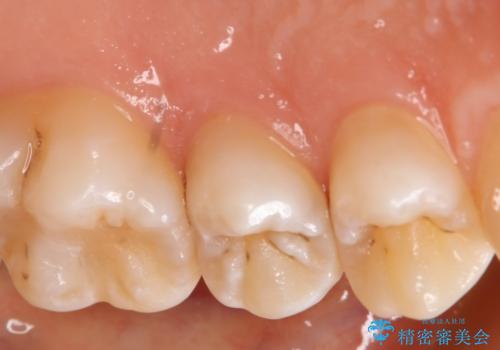

- 左上5番の虫歯治療を主訴に来院された患者様です。

セラミックでの治療を希望されたので形態・切削量を考慮しセラミックインレーでの治療を選択しました。

隣り合っている面(隣接面)は清掃がしづらく虫歯になりやすい場所です。

また、形態の再現が難しいのでインレーなどの補綴物での治療が第一選択となることが多いです。